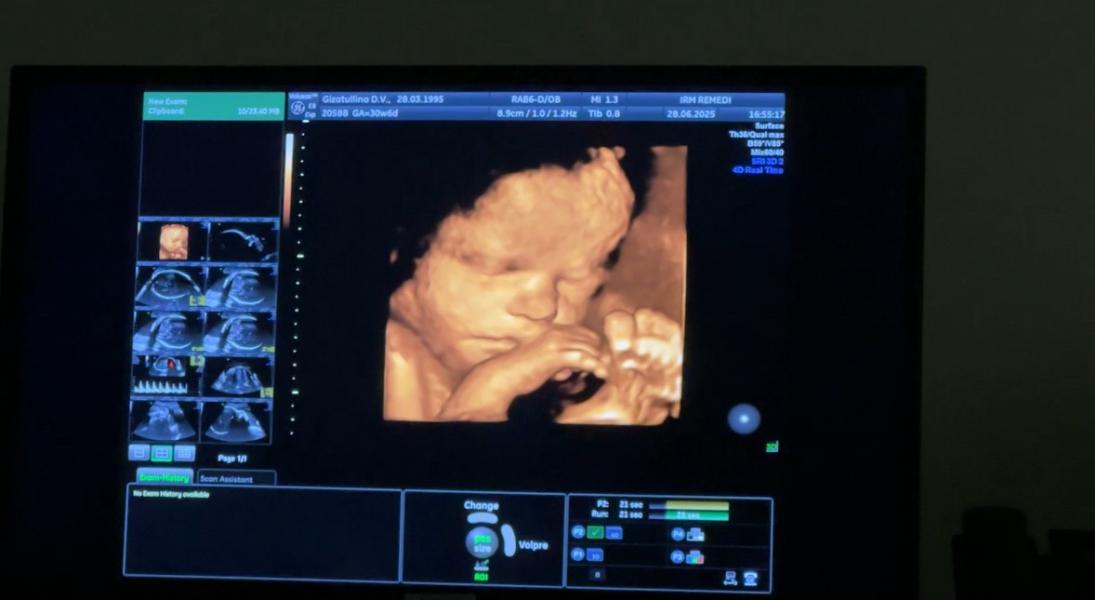

Была в REMEDI (метро Улица 1905г.), узист Справцева Алла Игоревна, благодарю девочки, кто её советовал ☺️🙏🏻

А сейчас ляля уже такая большая🥹прям новорожденный человечек❤️даже шевелюра говорит у неё уже есть 😍

Мои были в шоке от 3д узи😂Руся вообще думал, что узи будет черно белое😂а тут такое говорит ))))👀